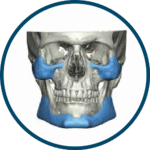

OMNIPORE® de Matrix Surgical es un implante poroso de alta densidad diseñado para reconstrucción cráneo-facial y cirugía estética. Fabricado en polietileno poroso, permite ser fresado, cortado o moldeado durante la cirugía para una adaptación precisa a la anatomía del paciente. Su estructura favorece el crecimiento tisular, promoviendo una mejor integración y estabilidad a largo plazo. Se suministra estéril y listo para su uso inmediato, evitando riesgos de contaminación al no requerir reesterilización.